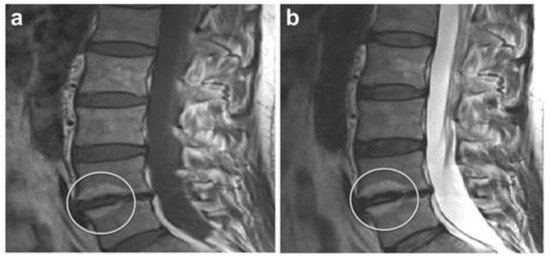

MRI scan of a human spine and lower back.

Degenerative Disc Disease (DDD)